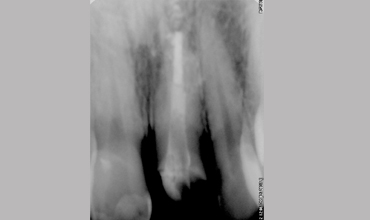

Management Of Fractured Central Incisor With Biological Post